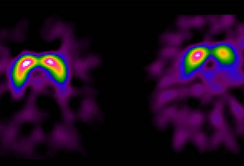

Zahlreiche Studien, unter anderem auch aus Innsbruck, belegen, dass viele Parkinson-Patient:innen schon vor dem Auftreten der ersten motorischen Symptome andere Dysfunktionen entwickeln. Im Frühstadium werden etwa die chronische Obstipation (Verstopfung), aber auch Stimmungsstörungen mit Depressivität oder Panikattacken beobachtet. Aber auch die Störung des Geruchssinns und die nächtliche REM-Schlafstörung können frühe Indikatoren für das Parkinson-Syndrom sein. „Mindestens 50 Prozent der Patient:innen zeigen bis zehn Jahre vor Beginn der Krankheit derartige Symptome“, bestätigt Prof. Poewe ein Forschungsergebnis aus einer, in Zusammenarbeit mit Forscherkolleg:innen in Barcelona durchgeführten Untersuchung. Die „prämotorische“ Phase kann Monate bis Jahre in Anspruch nehmen und bildet somit ein wichtiges Zeitfenster für die Frühdiagnostik. Diagnostisches Potenzial liegt aber auch in der Bildgebung: So konnte in mehreren Studien die prädiktive Relevanz von Ultraschallmerkmalen im Mittelhirn bestätigt werden.